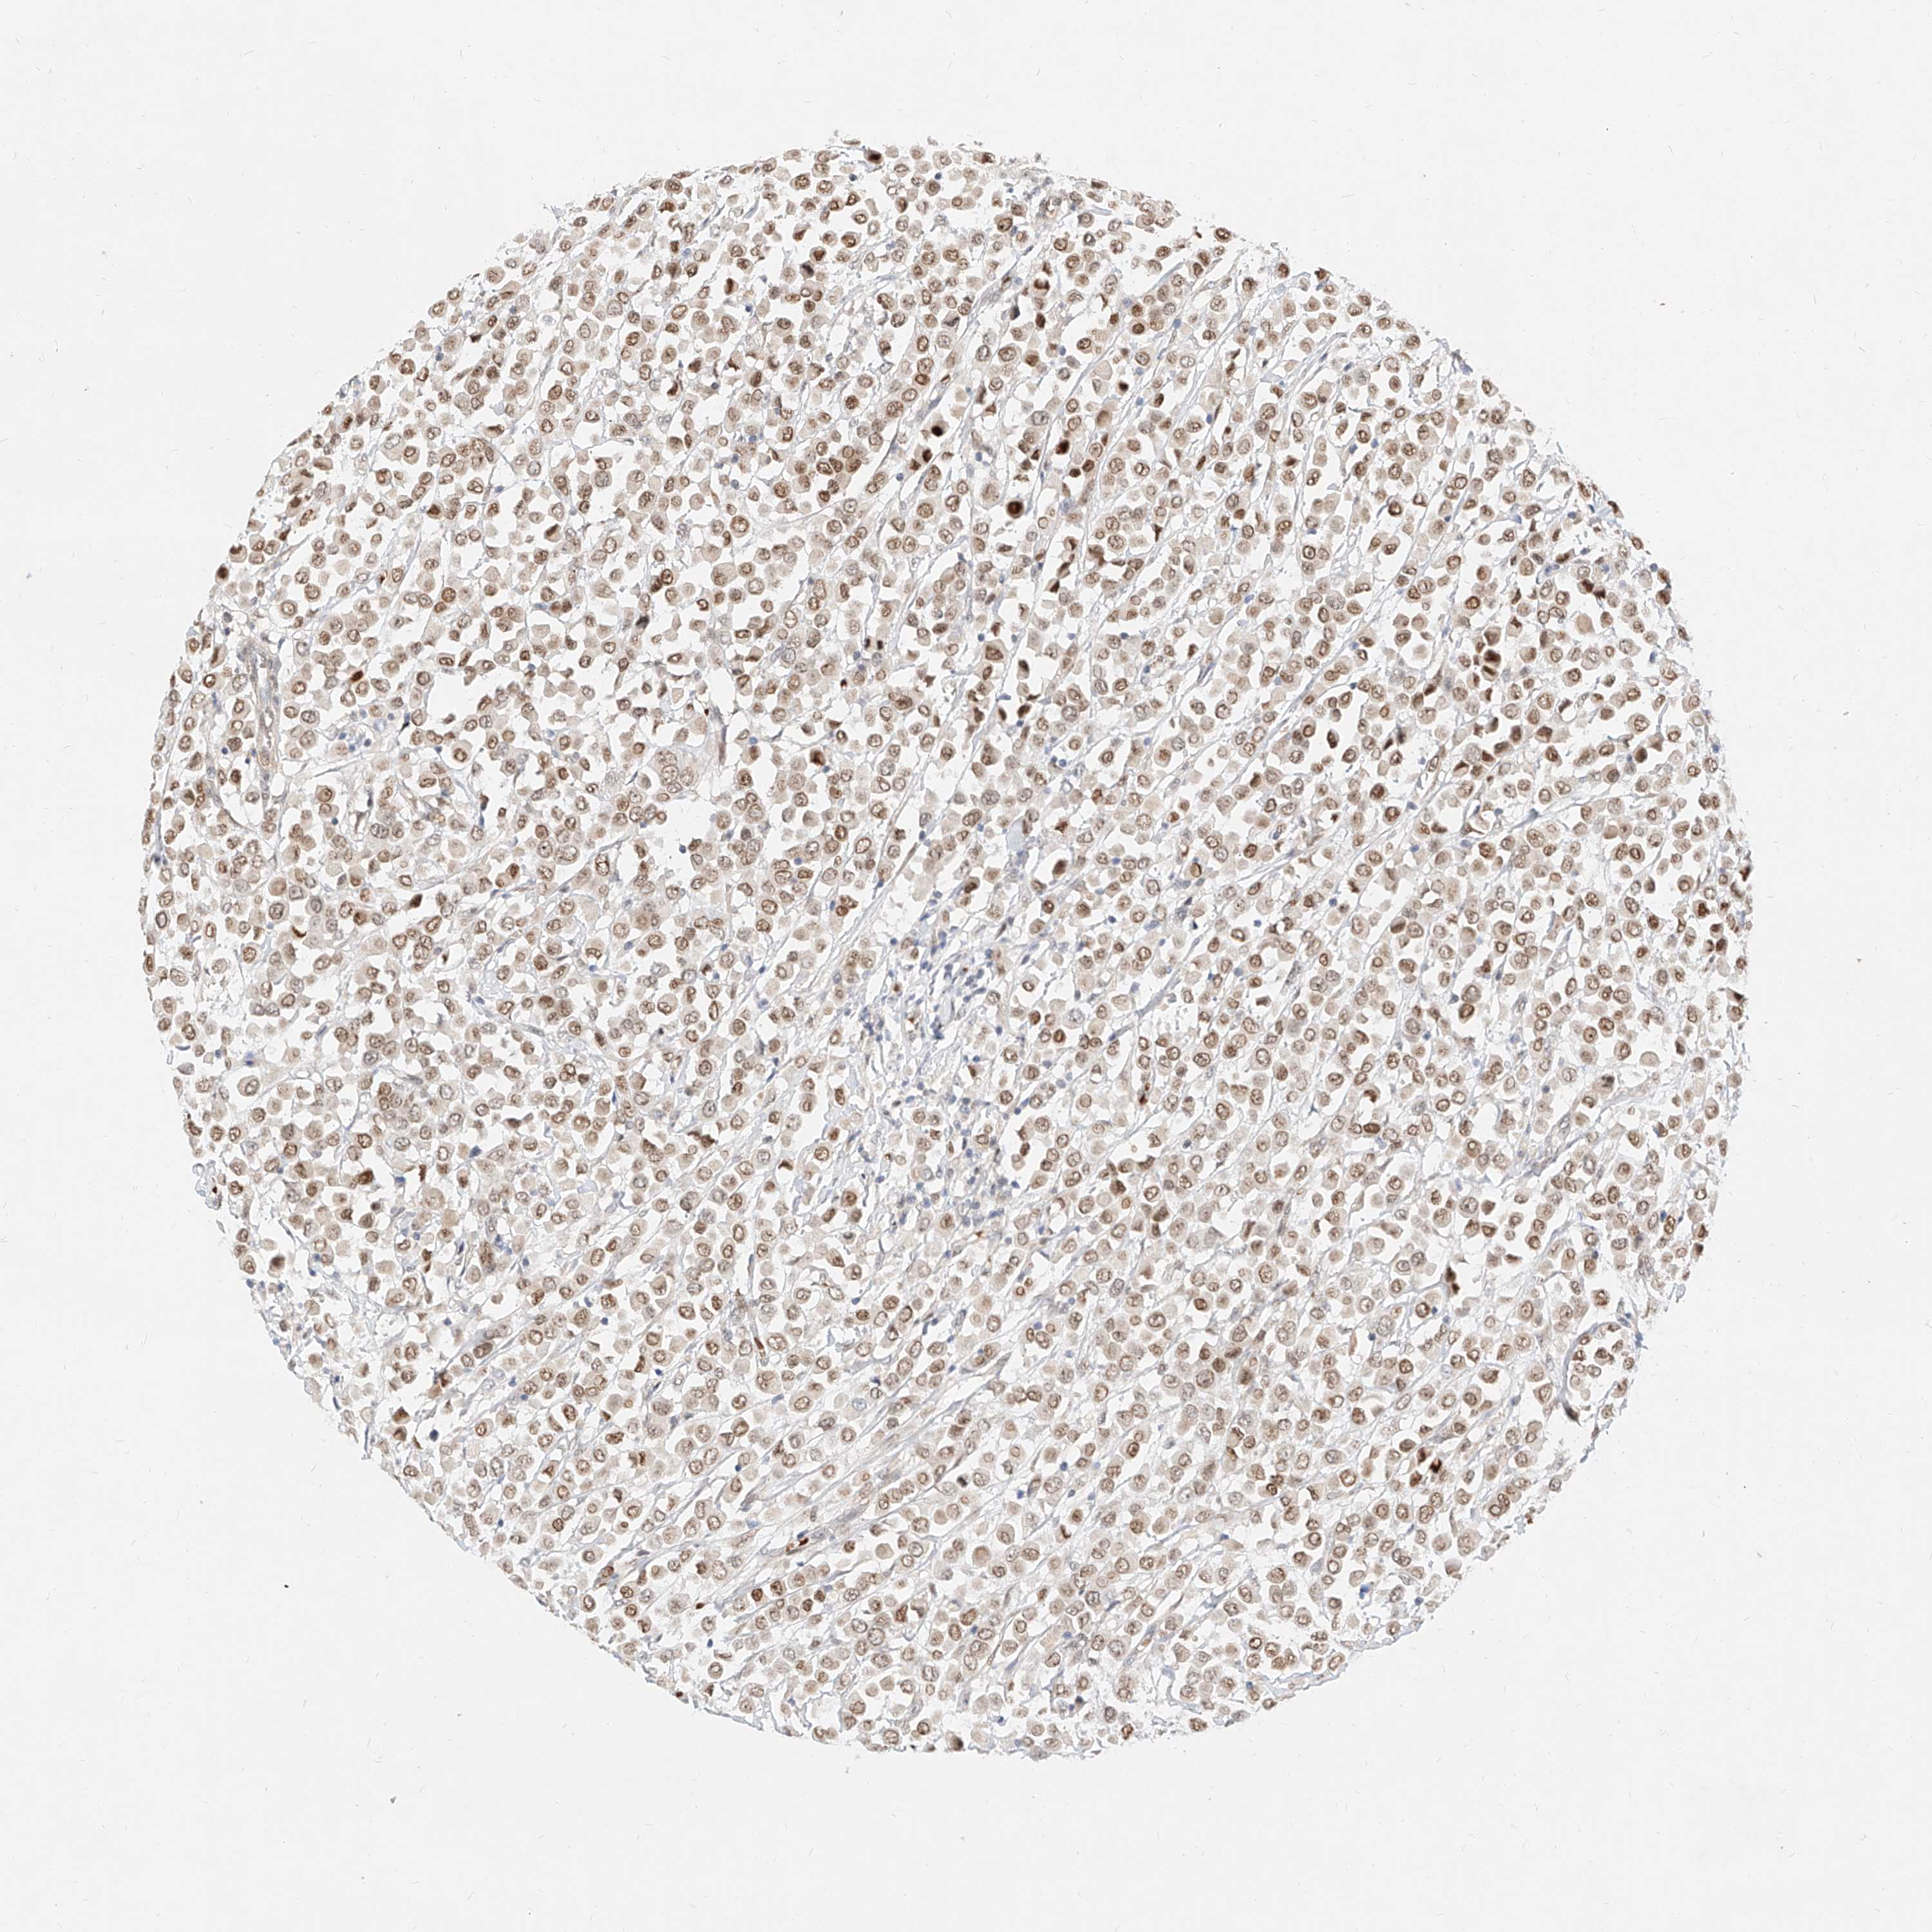

BRCA TCGA BRCA VALIDATION PROTEIN EXPRESSION

ANTIBODIES

AND

VALIDATION